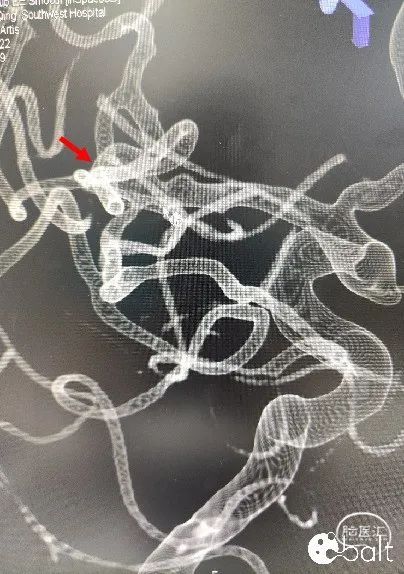

患者动脉瘤位于大脑中动脉M1分叉部,瘤颈累及M2段上干支和下干支;动脉瘤表面存在多处小的不规则凸起,破裂出血的风险相对较高,且有症状表现,需要手术干预。

瘤颈较宽,单一支架并不能完全覆盖瘤颈,填圈时有脱圈风险且达不到最佳治愈目的;为充分保护瘤颈及分支血管使手术顺利进行,行“Y”型支架植入,辅助弹簧圈栓塞。

支架放置如图所示:

上干支血管成角较锐,且相对下干支更粗,更直,适合放置相对较长的支架,以方便覆盖更多瘤颈。下干支偏细,且迂曲的远端不利于支架释放,适合短支架,便于打开和保护瘤颈。